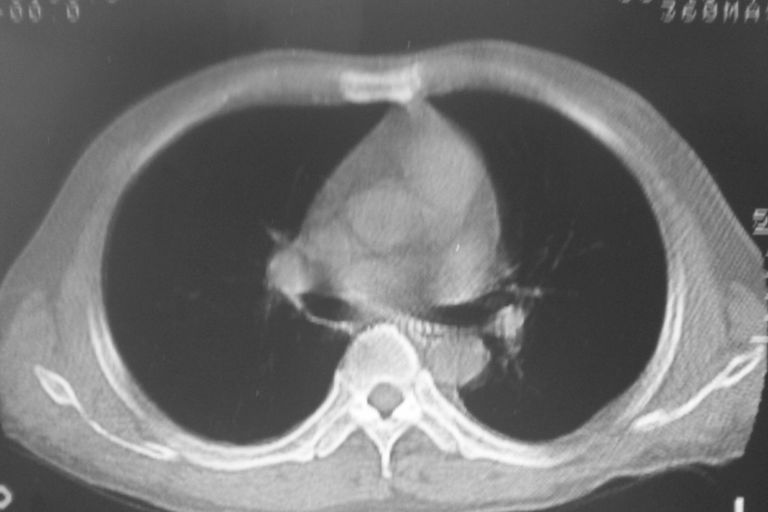

患者 男 50岁 无痛性咯血3天,无其他不适.

2心包积液

2、心包积液

2 心包积液。

左下肺结节状软组织密度影,一个边缘有卫星病灶,邻近胸膜增厚.另一个有毛刺.心影周围水样密度影环绕.考虑:

1.肺癌可能.肺tb待排.

2.左侧胸膜增厚.心包积液.